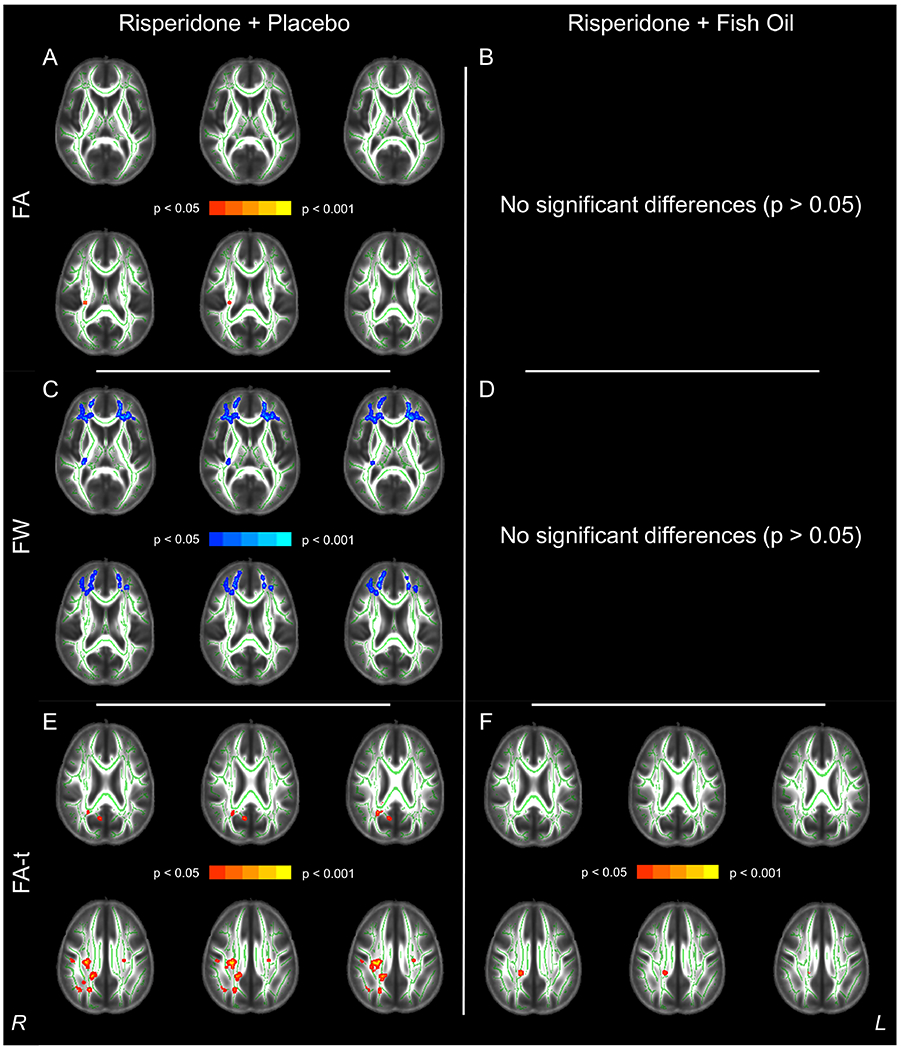

There were no treatment group differences at baseline or follow-up regarding FA, or the Free Water Imaging measures FA-t and FW. Further, independent groups t-tests on the difference maps were not significant for the diffusion measures. When assessing within-group differences, individuals who received risperidone + placebo demonstrated significant reductions in FA at the time of their follow-up scan (n = 8, pFWE < 0.05) in the right posterior limb and right retrolenticular part of the internal capsule as well as the right posterior corona radiata affecting 0.31% of the entire skeleton. Free Water Imaging revealed reductions in FA-t mainly in the splenium, right posterior and superior corona radiata (affecting 3.05% of the entire skeleton), as well as robust increases in FW (affecting 17.53% of the skeleton) that were most evident within the frontal lobes (see Figure 3). In contrast, individuals receiving risperidone + FO demonstrated no significant changes in FA or FW and a much more limited reduction (0.27% of the skeleton affected; n = 10, pFWE < 0.05; Figure 3) in FA-t compared to the change in FA-t observed in the risperidone + placebo group.

Figure 3.

Summary of Within-Subjects Analysis Findings for Reductions in Fractional Anisotropy (FA, Red, Panels A and B), Increases in Free Water (FW, Blue, Panels C and D) and Reductions in Fractional Anisotropy of the Tissue (FA-t, Red, Panels E and F) over the Course of the Treatment Trial in the Risperidone + Placebo Group (Left Column) versus the Risperidone + Fish Oil Group (Right Column). All images are presented in radiologic convention.